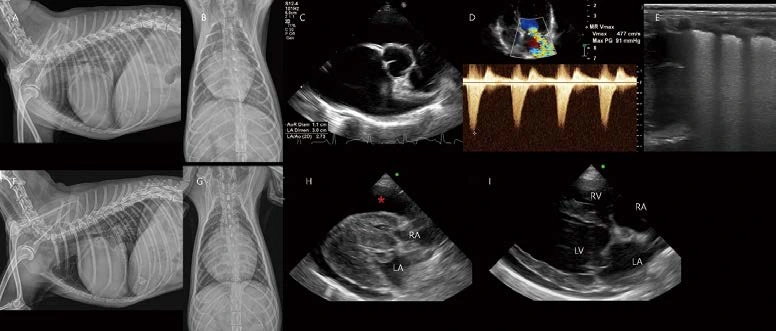

13살 수컷 26.5kg Golden retriever가 급성 기력저하로 내원하였습니다. 심한 노력성 호흡 상태에 혈압은 80mmHG였습니다. 흉부방사선 검사에서 폐야 전반에 걸친 작은 연조직 밀도 결절성 음영이 관찰됩니다(A, B). 심장은 globoid cardiomegaly with sharp contour를 보입니다(A, B). 폐초음파에서 폐전이가 고려되는 결절성 음영이 관찰됩니다(C). 심초음파에서 다량의 심낭수가 관찰되며(D, *), 이로 인한 cardiac tamponade(우심실, 우심방 collapse, CVC plethora, 소량의 복수)가 관찰됩니다. 일반적으로 스캔하는 Right parasternal four chamber long axis view, short axis view에서는 종괴 음영이 관찰되지 않으나, oblique로 right auricle을 스캔하면 right auricular wall 내외로 bulging된 결절성 종괴 음영을 찾을 수 있습니다(E, F). 이 환자는 심낭수 천자 및 세포학적 검사에서 primary cardiac hemangiosarcoma로 확인되었습니다. Hemangiosarcoma는 우심방, 우심이에서 잘 발생하는데, 심초음파에서 right auricle 병변은 놓치기가 쉽습니다. 심낭수가 있을 경우에는 스캔이 잘 되는 편이나, 심낭수가 없을 경우 right auricle 또는 left auricle 병변을 간과하기 쉬우므로 심초음파 스캔 시 주의가 필요합니다.

16살 중성화 암컷 10.5kg Beagle의 건강검진에서 심장 종양이 관찰되어 의뢰되었습니다. 흉부방사선 검사에서 right side cardiomegaly 및 heartbase 또는 aortic body 위치에서 둥근 밀도 증가 영역이 관찰됩니다(A, B). 심초음파에서 소량의 심낭수 및 heartbase 위치의 커다란 종괴가 관찰됩니다. CT 검사에서 우심방과 전대정맥을 압박하는 커다란 이질적 heartbase tumor가 관찰됩니다(C, D E, F, G). 또한 , heartbase tumor와 관련하여 폐혈관 내 혈전(G), left bronchoesophageal arterial hypertrophy 소견(D)도 추가로 관찰됩니다. Heartbase tumor에는 chemodectoma가 주로 보고되어 있습니다. Brachycephalic dogs에서 incidental findings으로 관찰되는 경우가 많으며, Non brachycephalic dogs에서도 은근히 관찰됩니다. 종괴의 정확한 진단을 위해서는 조직 검사가 필요하나, 현실적으로 조직 검사가 어려운 경우가 많기 때문에 모니터링을 통해 가진단을 내리게 됩니다. Chemodectoma는 일반적으로 benign하나, RA, CrVC 등 주변 구조물을 심하게 압박하는 경우(C)에 cranial vena cava syndrome의 증상을 보일 수 있습니다. 또한 left bronchoesophageal arterial hypertrophy(D), esophageal varices, 혈전(G) 등의 complications이 발생할 수 있습니다. 환자 경과에 대한 면밀한 모니터링이 필요합니다. CT에서 Incidental finding으로 heartbase tumor가 관찰되었던 환자들의 흉부방사선 검사를 다시 평가하면, 안 보이던 종괴 음영이 잘 보이게 되는 ‘아차!’ 경험을 하게 됩니다. 다양한 이로 CT 촬영을 하는 환자들을 기존 방사선 검사 또는 초음파 검사와 비교하다 보면 많이 배우게 되는 것 같습니다.

15살 중성화 암컷 2.71kg Maltese 환자가 호흡곤란으로 응급 내원하였습니다. 1년 전에 유선 종양 수술 병력이 있었습니다. 호흡수 108, 혈압 80, 심청진 시 muffled sound가 확인되었습니다. 흉부방사선 검사에서 폐엽 전반에 걸친 다수의 결절성 음영이 관찰됩니다. 또한 globoid cardiomegaly가 관찰됩니다. 심비대에 비해 폐혈관은 얇게 관찰되어 pulmonary hypoperfusion 상태가 고려됩니다(A, B). 폐초음파에서 다수의 폐 전이(균질한 저감쇠, 한계가 명료한 둥근 결절성 음영) 소견이 관찰됩니다(E, 화살표). 심초음파 검사에서 다량의 심낭수가 관찰됩니다(C, D, *). 심낭수로 인해 우심실, 우심방의 심한 collapse가 관찰됩니다. 심낭막에서는 부분적으로 불규칙한 결절성 비후 영역이 관찰됩니다(C, D, 노란 화살표). CVC plethora(F), splenic mass(G)가 관찰됩니다. 이미 유선 종양에 의한 전신 전이 상태로 생각되었으나, 심한 cardiac tamponade로 응급 상태였으므로, 수액을 공급하면서, 매우 낮은 속도로 조심스럽게 심낭수 천자를 실시하였습니다. 약 100ml의 혈액성 심낭수 천자를 진행하면서 환자는 호흡이 편해지는 듯하였으나, 갑자기 CPA 가 발생하였습니다. Atropine, epinephrine에 심박, 자발 호흡이 돌아왔으나, 혈압은 40mmHg였고, Dobutamine CRI, 수액 shock dose로 유지하는데, 혈압 30mmHg이 떨어지면서 다시 CPA 가 발생하였습니다. 삽관 이후 벤틸레이터를 유지하면서 응급 약물 처치하였으나, 반응이 없었고, 안타깝게도 심낭수 천자 이후 약 1시간 후 사망하였습니다.